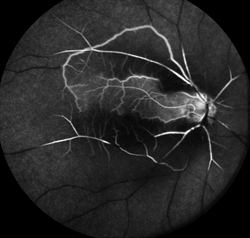

The whitening of the retina generally lasts 4 to 6 weeks before fading. Fluorescein angiography (FA) shows a delay in filling of the retinal arteries. (Figure 3) Optical coherence tomography (OCT) provides detailed images of the central retina, and shows swelling in the inner layers of the retina in the affected area, which over time atrophy, becoming much thinner than normal.

Figure 3. Fluorescein angiogram of CRAO showing sparing of the cilioretinal artery. Courtney Crawford, MD. Retina Image Bank 2017; Image 26792. ©American Society of Retina Specialists. |